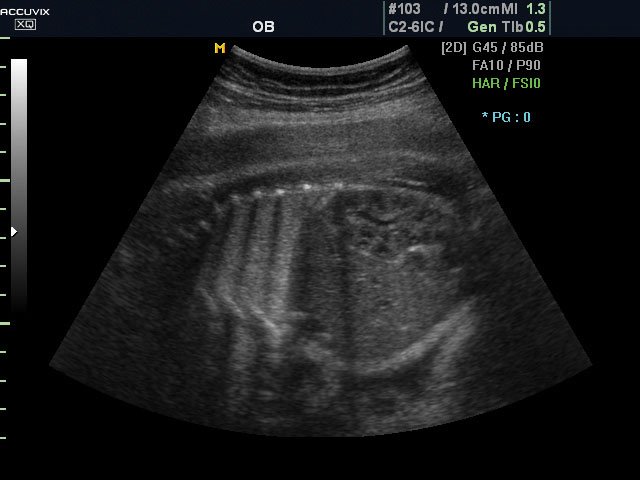

DMR - фильтр эхограмм подобный MRI

DMR™ (Dynamic like Magnetic Resonance) - фильтр ультразвукового изображения с алгоритмом подобным MRI (магнитный резонанс), включает в себя трёхуровневую фильтрацию: объектов, текстур и областей, пикселей. Клиническое применение - исследования сосудов, исследования костных структур плода, скрининг сердца, мониторинг биопсии.

Брюшная полость плода в продольной плоскости, 2D (без Dynamic MR™).

Брюшная полость плода в продольной плоскости, 2D (в режиме Dynamic MR™).

Сильные стороны DMR: фильтрация в реальном времени, подавление спекл-шумов и артефактов, усиление контуров, получение более четких и контрастных ультразвуковых изображений на границе сред разной эхо-плотности.